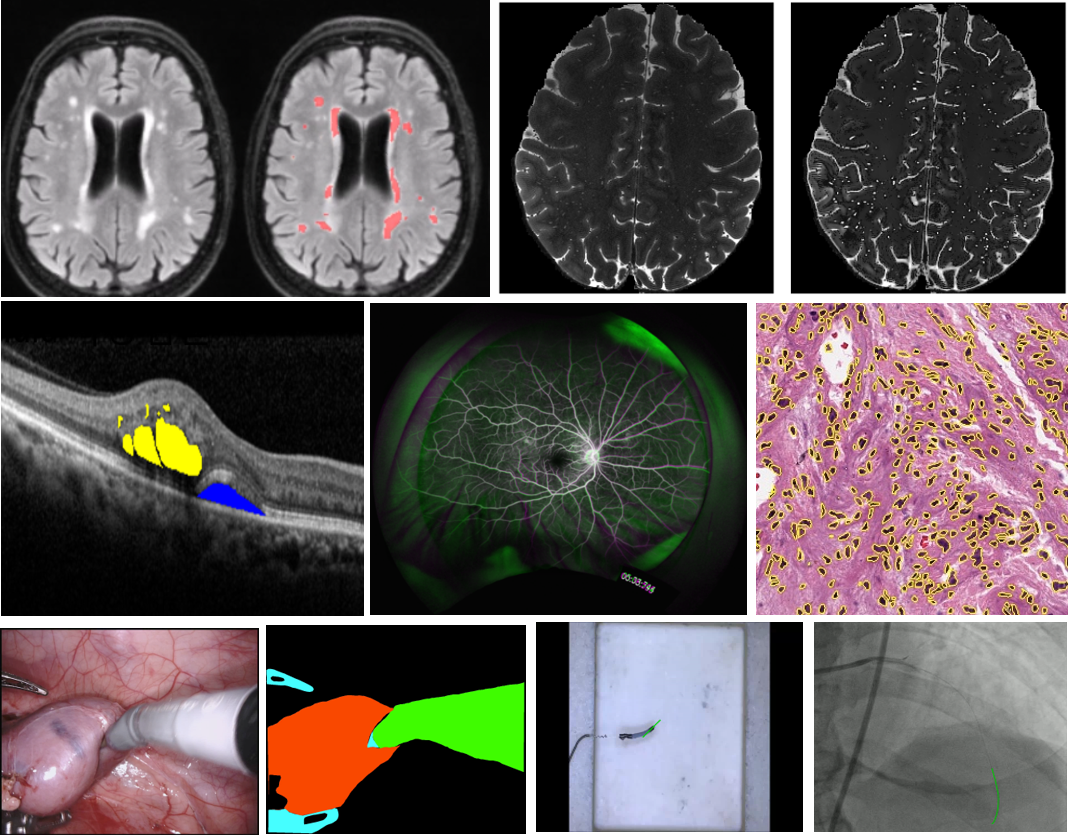

- Medical Image & Signal Processing Lab

We are interested in the development of advanced artificial intelligence (AI) algorithms for medical image analysis and robot intelligence. The following studies are being conducted.

- Computer vision / Machine learning / Deep learning- Medical image analysis (classification, enhancement, segmentation, registration)- Pathology image analysis- Robot tracking- Bio signal processing